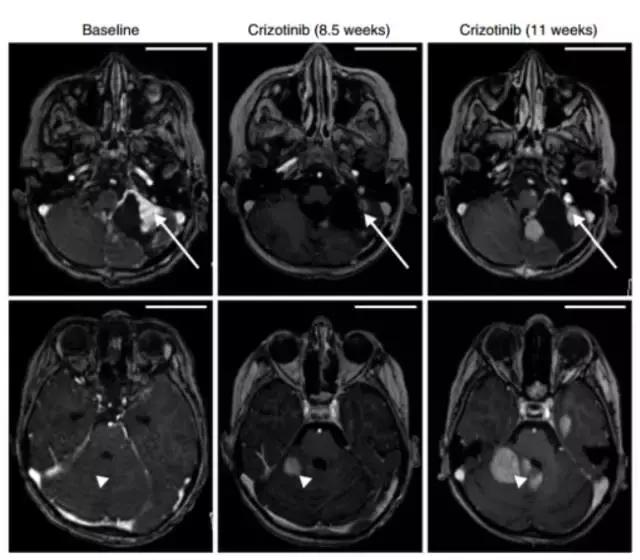

儿童胶母中较常见的致癌基因融合约占10%,MET基因融合为其中的典型,下图左为MET基因融合的类型。MET融合激活MAPK信号通路,破坏细胞周期调控,诱导肿瘤进展。MET*制剂抑**的模型研究发现其能抑制MET突变的肿瘤生长。

MET融合形式及MET*制剂抑**治疗效果

一名8岁的男孩,具有复发的小脑胶质母细胞瘤,伴随PTPRZ1-MET基因融合,使用MET*制剂抑**克唑替尼治疗后,11周内肿瘤显著减小(如右图上方长箭头所示),此位置症状缓解,但其他的位置发生新的耐药病灶(如右图下方三角箭头所示),由此可见综合治疗可能是达到持久临床获益的必经之路。